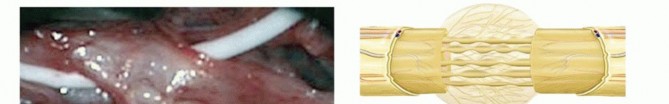

To bridge this defect, autologous nerve grafting is the gold standard. The sural nerve is the most common donor, harvested via a minimally invasive step-cut technique or endoscopic approach to minimize donor-site morbidity.

The harvested graft is reversed (to prevent axonal branching into dead-end donor branches) and cut into cables matching the length of the defect.

These cables are meticulously coapted to the proximal and distal stumps of the resected fascicles using 9-0 or 10-0 nylon sutures placed strictly in the epineurium or perineurium, ensuring a tension-free repair. Fibrin glue may be used to augment the repair and reduce the required number of sutures, thereby minimizing foreign body reaction and subsequent scarring.